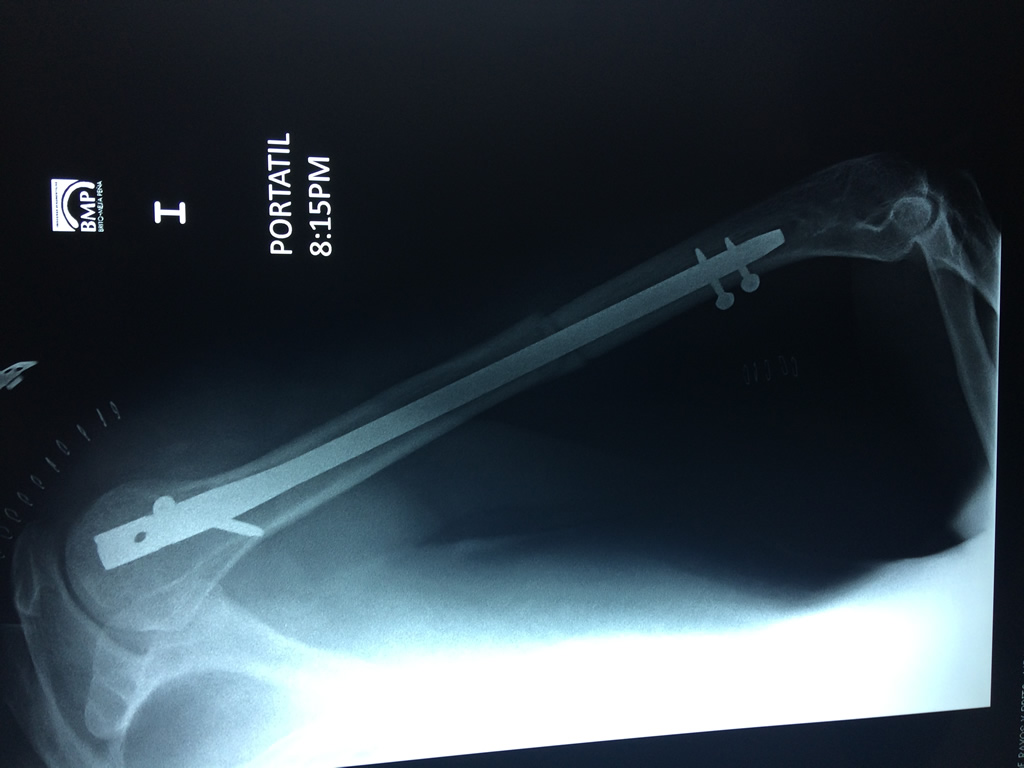

Húmero - Húmero

El Húmero (en latín, humerus) es el hueso más largo de las extremidades superiores en el ser humano. Forma parte del esqueleto apendicular superior y está ubicado en la región del brazo. ... El extremo proximal del húmero tiene la cabeza, cuellos quirúrgico y anatómico y tubérculos mayor y menor.